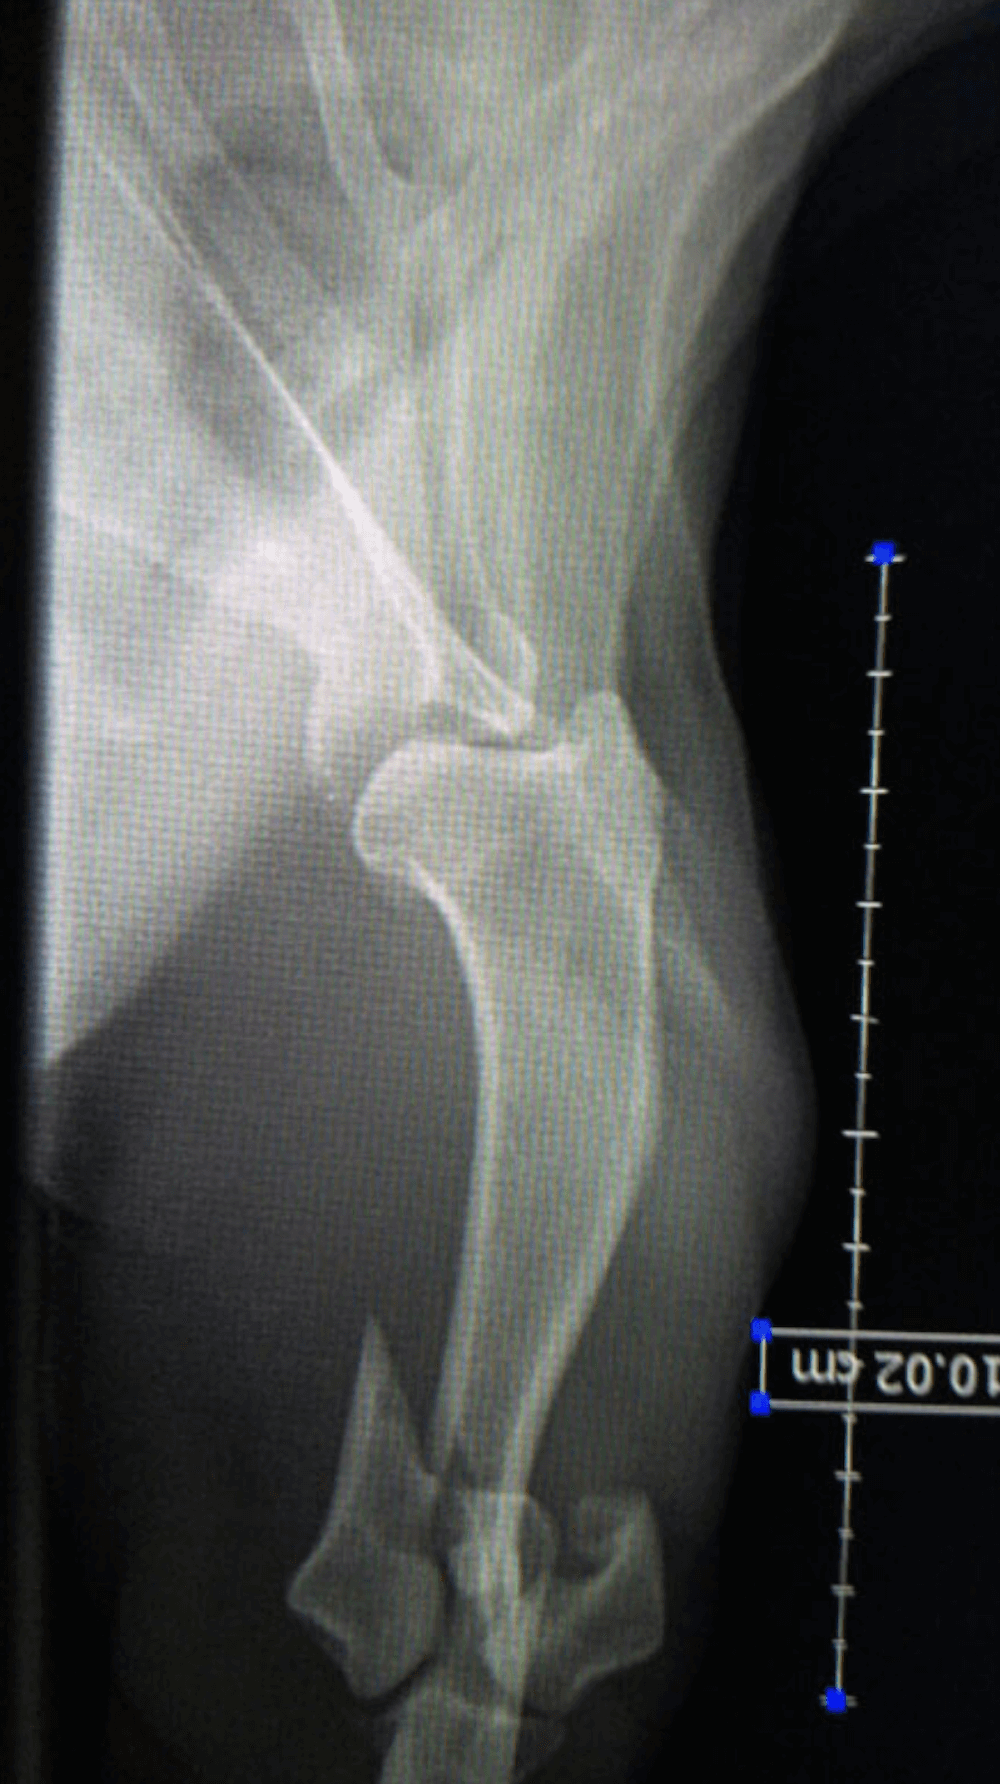

Y Fracture Repair

In a Springer Spaniel.